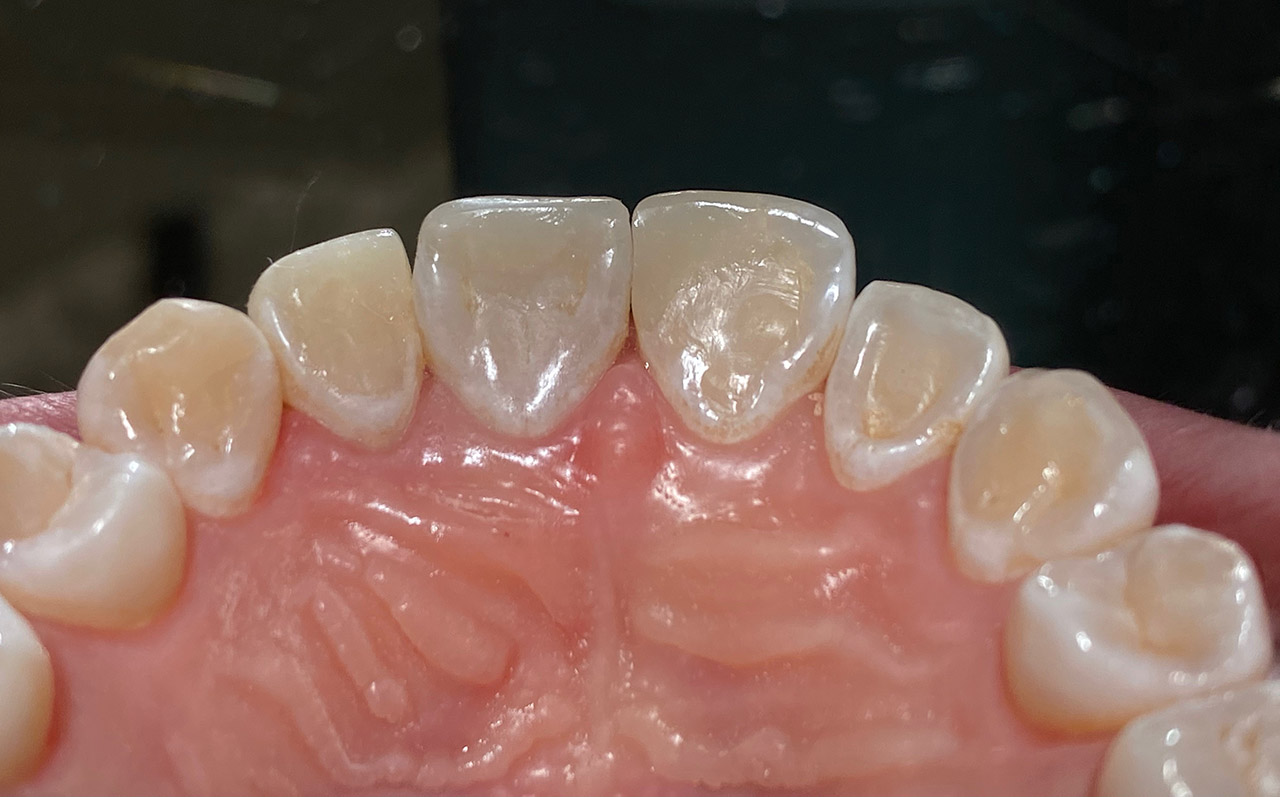

Aplasien/Nichtanlagen, dadurch bleibende Milchzähne, Diasteme/Zahnlücken,

Bleaching/Bleichen, Positionierung der Zähne/Kieferorthopädie (Dr. Maija Eltz), Verblendung mit Veneers/Keramikschalen.